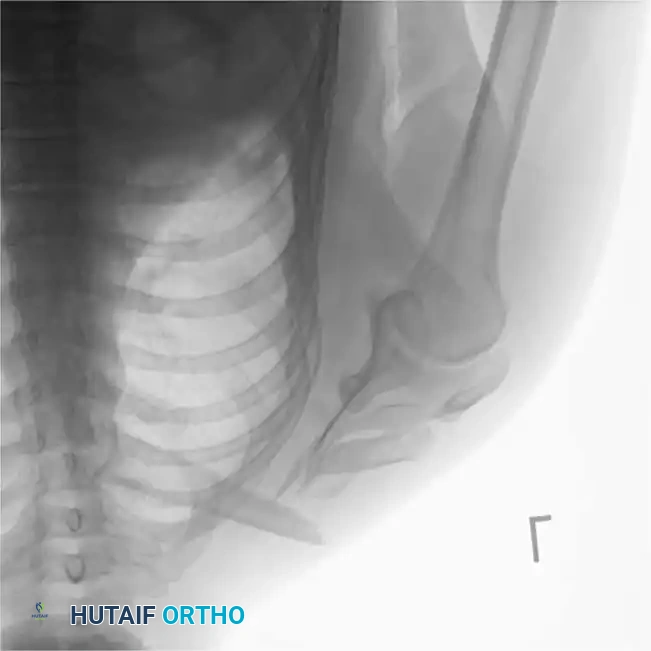

5. The Floating Shoulder

A "floating shoulder" occurs when there are ipsilateral fractures of the clavicle and the surgical neck of the scapula, disrupting the Superior Shoulder Suspensory Complex (SSSC).

Fig. 54-2: Biomechanics of the floating shoulder. The weight of the arm and the pull of the shoulder girdle muscles rotate the glenoid fragment anteromedially, leading to severe drooping of the shoulder.

This double disruption renders the scapular fracture highly unstable. Herscovici et al. recommended ORIF of the clavicular fracture with a 3.5-mm plate to indirectly stabilize the scapular neck, preventing malunion and shoulder ptosis.

However, Edwards et al. reviewed 20 patients with floating shoulders and achieved union with nonoperative treatment in 19 cases, noting excellent functional results if displacement was less than 5 mm. Therefore, widely displaced fractures (>5 mm to 1 cm of translation or severe angulation) require operative fixation of the clavicle, and occasionally the scapula as well.